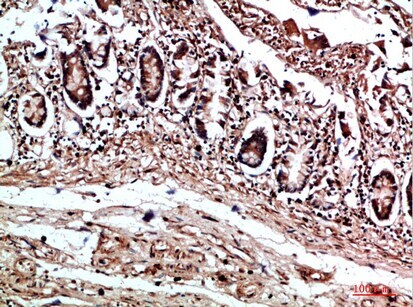

Supportive validation

- Submitted by

- Invitrogen Antibodies (provider)

- Main image

- Experimental details

- Immunohistochemical analysis of COL17A1 in paraffin embedded human colon tissue using COL17A1 Polyclonal Antibody (Product # PA5-67897) at a 1:200 dilution.